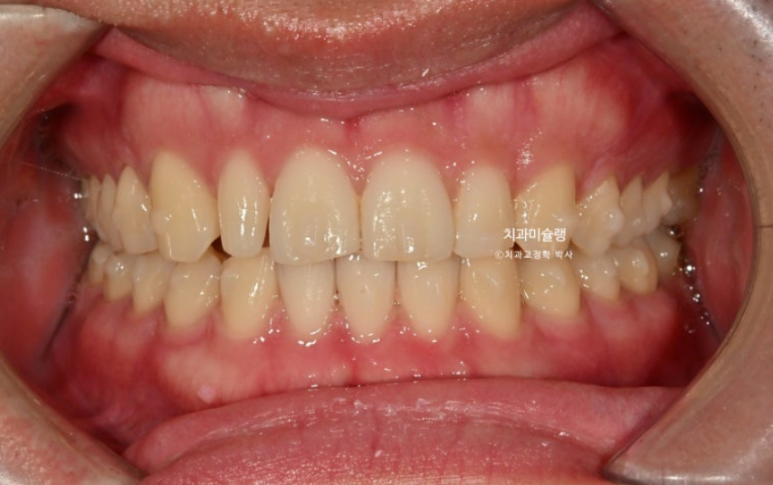

24.03~25.11